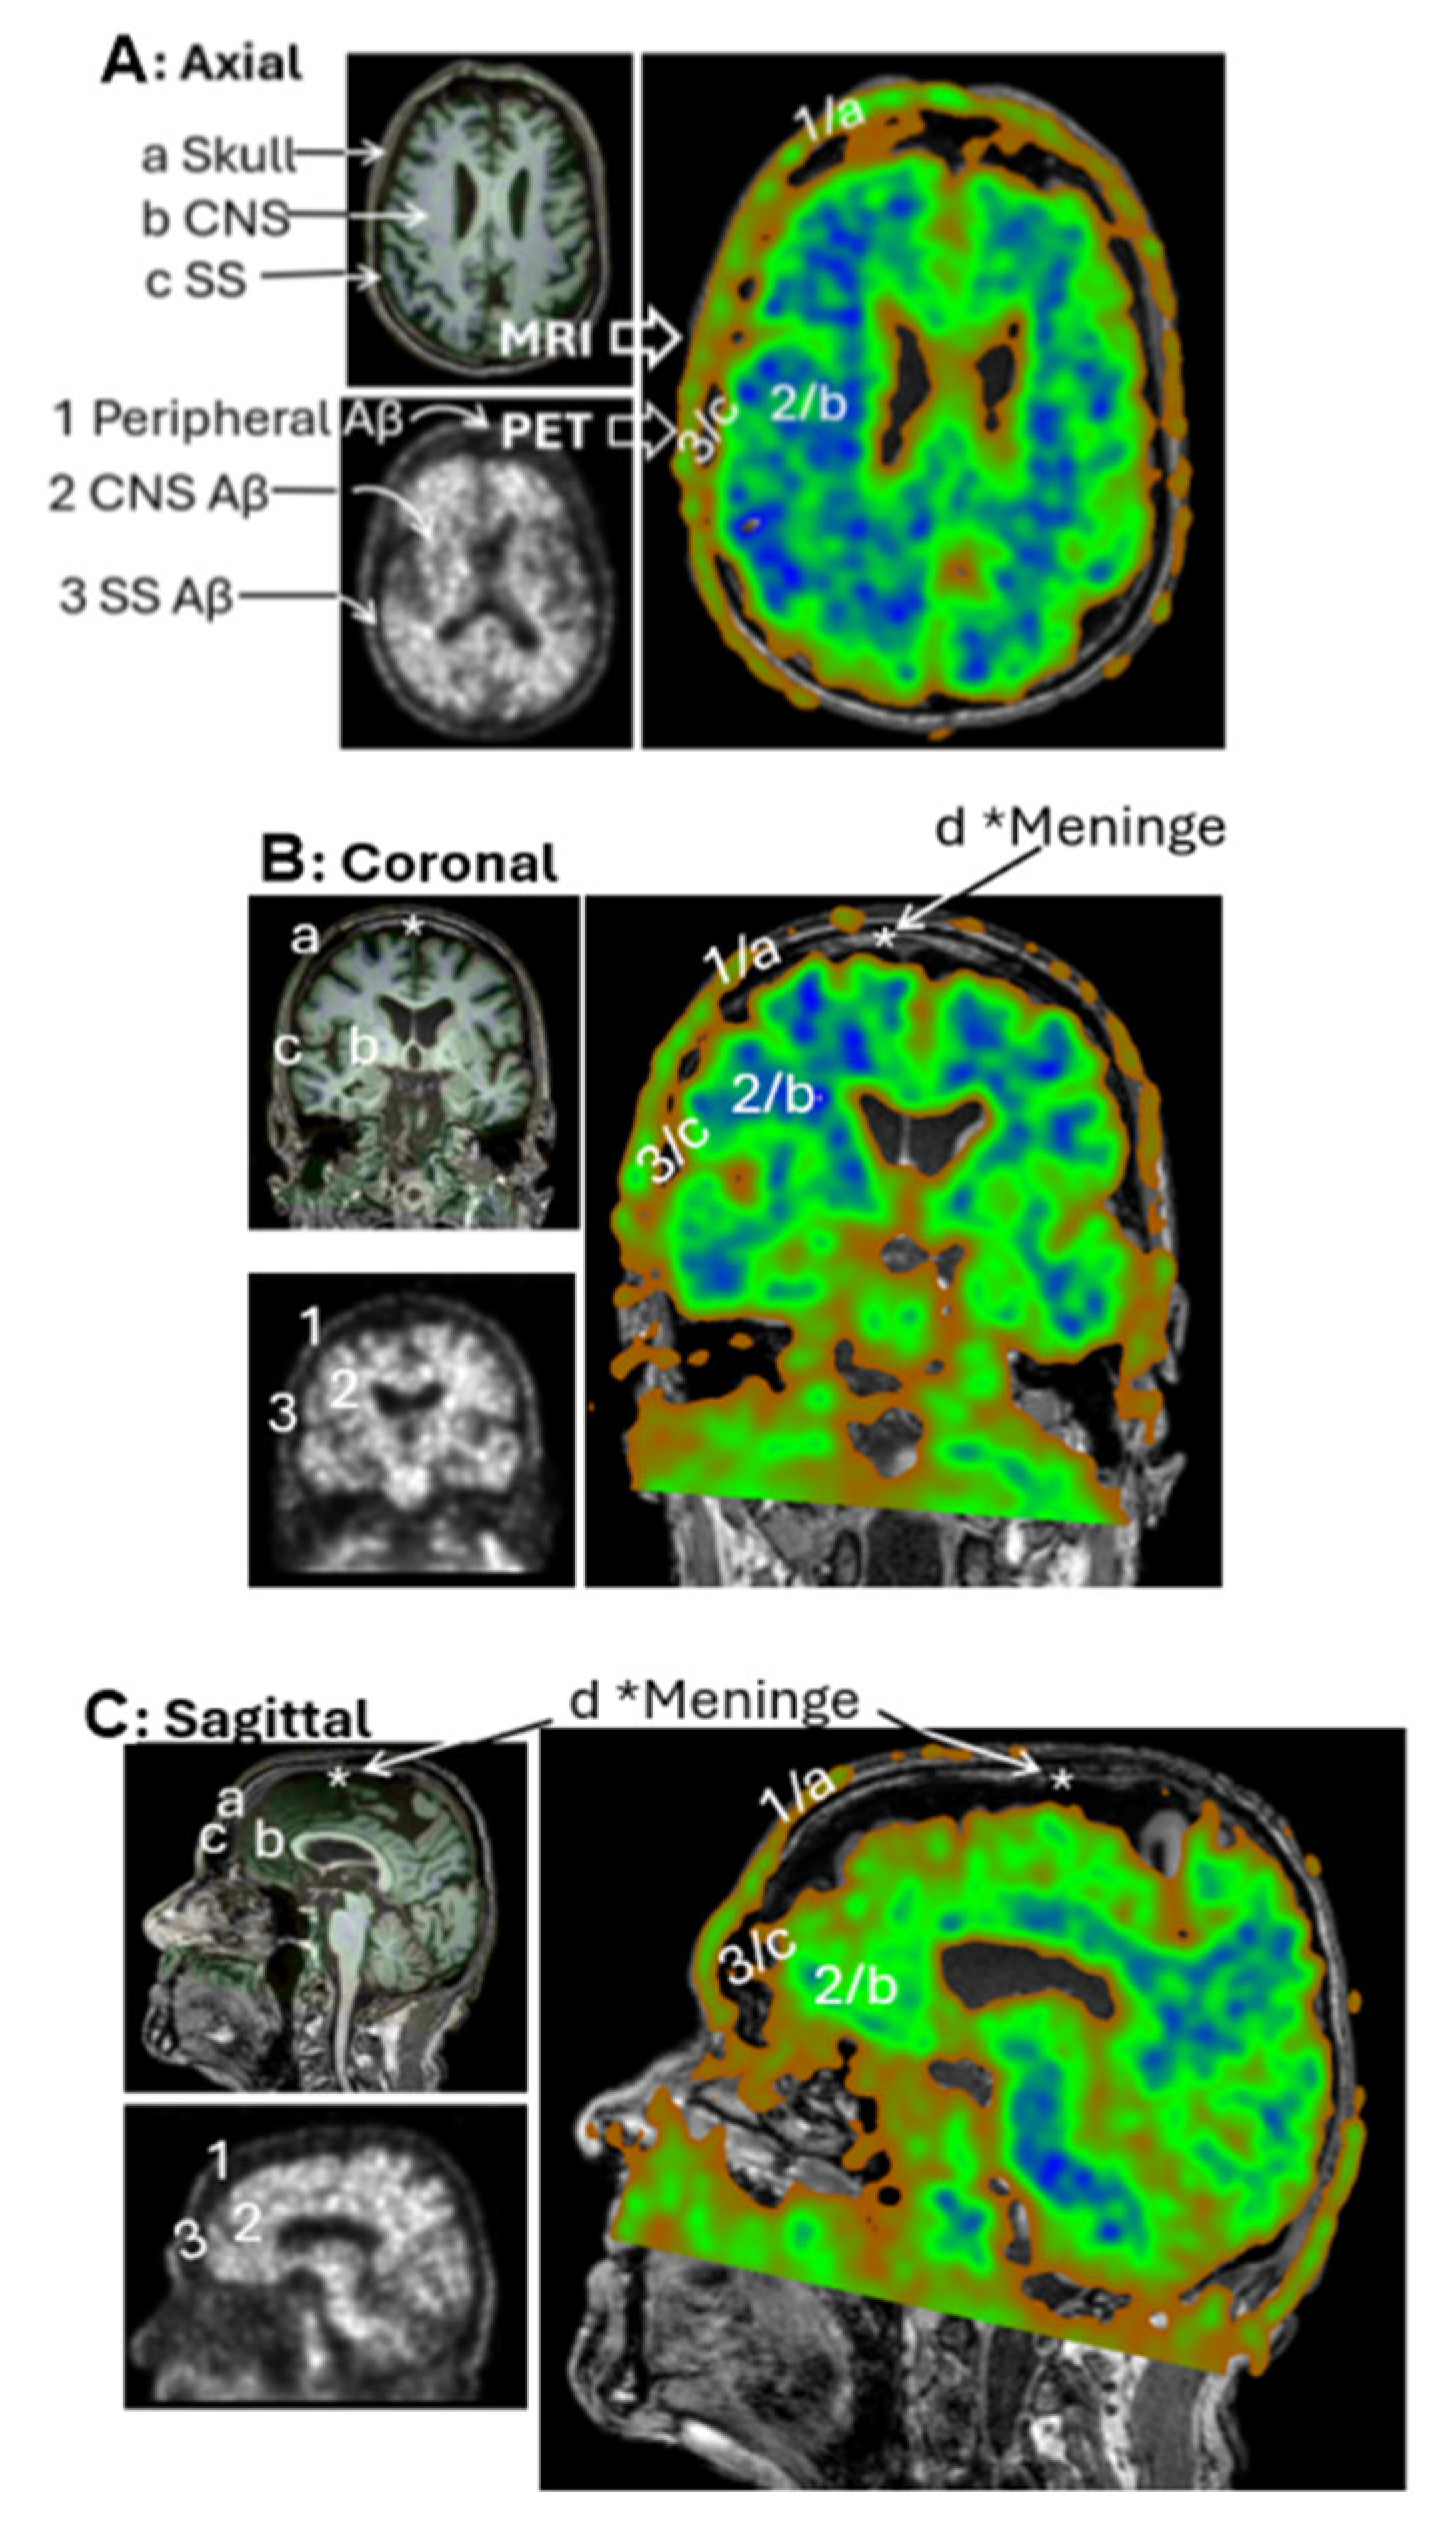

In raw PET imaging, Aβ signals are detectable in both the brain parenchyma and extracranial regions. However, extracranial signals have largely been overlooked and remain poorly characterized. To begin addressing this gap, we sought to understand the spatial relationship between extracranial Aβ deposits and anatomical structures of the head. This was achieved by co-registering PET images with MRI scans from the same individuals. Figure 4A presents an axial view of the co-registered images, revealing that extracranial Aβ deposits are spatially co-localized with the skull. This pattern of colocalization was consistently observed in the coronal (Figure 4B) and sagittal (Figure 4C) views. These findings suggest that PET signals in superior regions are anatomically associated with the skull, rather than with meningeal structures.

Figure 4. PET/MRI Coregistration. Representative MRI (left top panels) and PET scans (left bottom panels) from the CU-3 individual. Coregistration was conducted with 3D Slicer to set PET as the moving image (blue-green right panels) and MRI as the fixed reference (dark-gray right panels). Anatomical regions identified on MRI include a—Skull, b—Central nervous system (CNS), c—Subarachnoid space (SS), d—Meninges. Corresponding regions identified on PET include 1—extracranial Aβ signal, 2—CNS signal, 3—SS signal. Subpanels: (A) Axial view, (B) Coronal view, (C) Sagittal view. Extracranial Aβ signals are spatially aligned with the skull, not the meningeal regions.